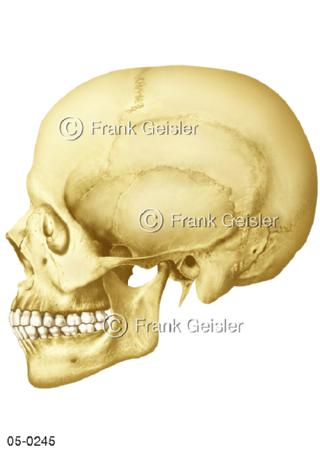

Bildergalerie Skelettsystem

Bilder zum Skelettsystem zeigen die Stützstruktur des menschlichen Körpers, die Knochen, eine besonders harte Form des Bindegewebes und Stützgewebes, welche das menschliche Skelett bildet, die Knochen des Stammes, der Extremitäten sowie der Gelenke